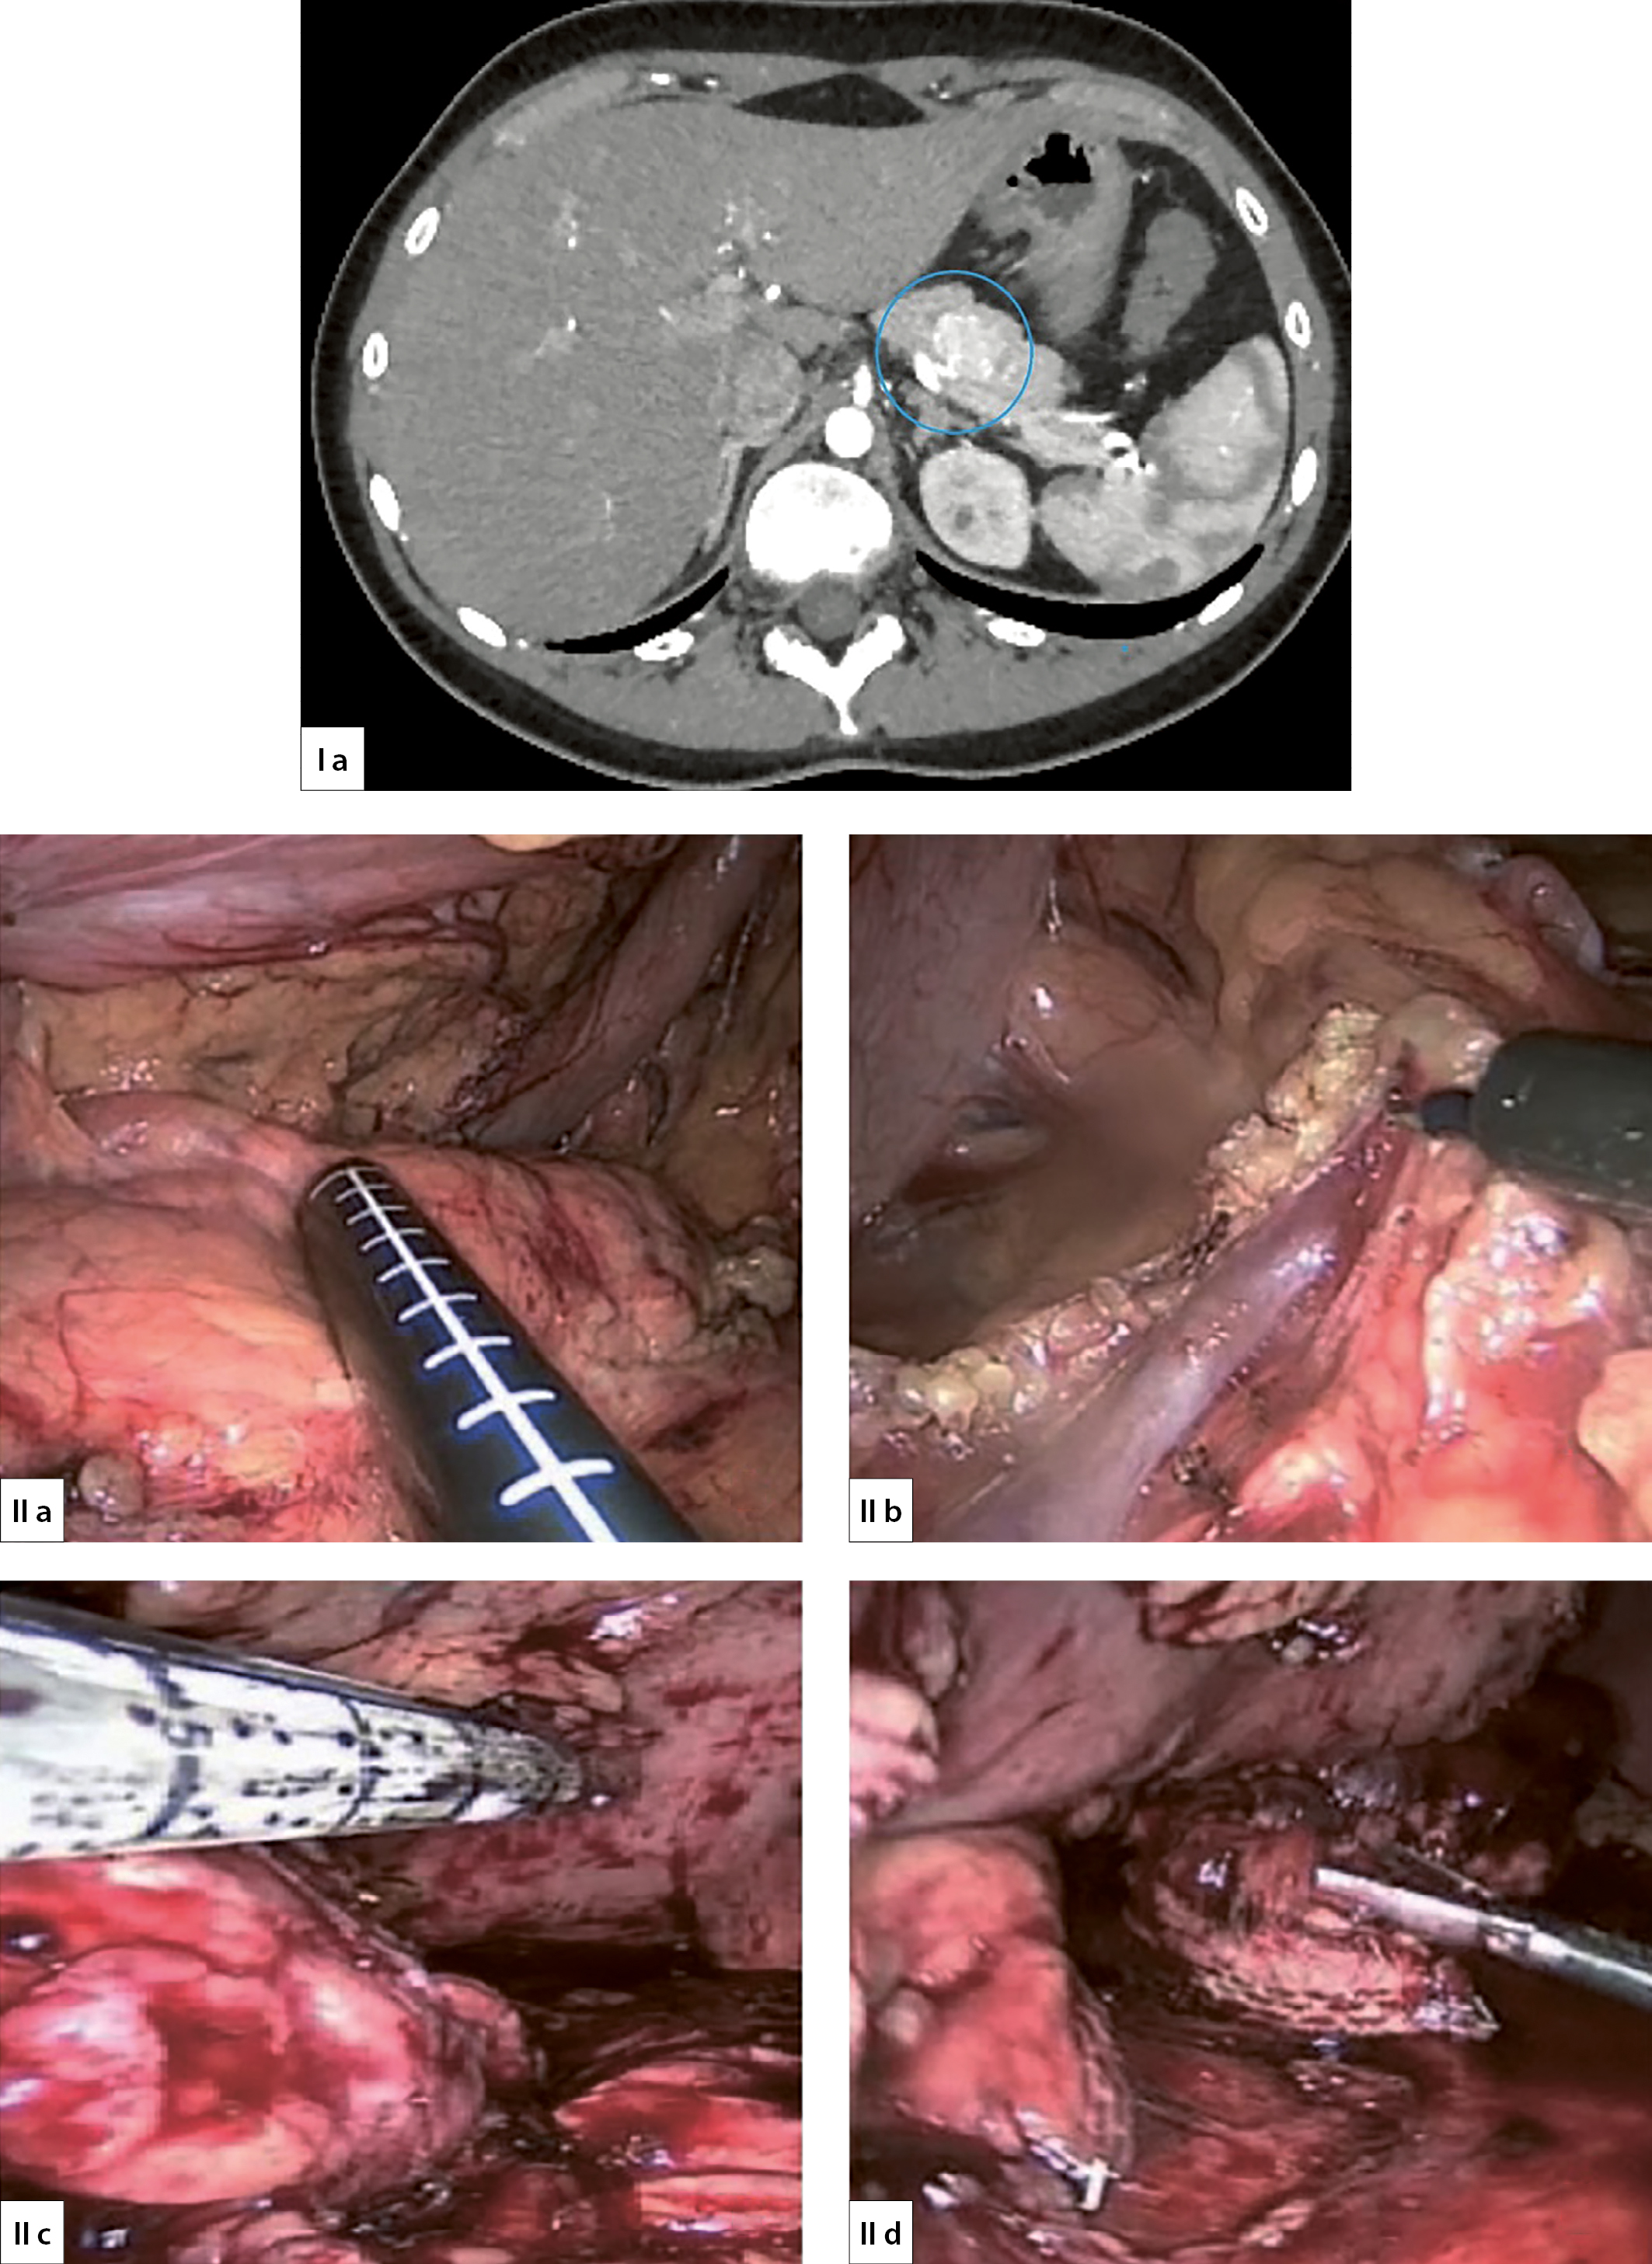

2. Рисунок 2. Лапароскопическая дистальная резекция ПЖ с сохранением селезенки (I — КТ инсулиномы в области хвоста ПЖ, II a — интраоперационное УЗИ, II b — выделение сосудов селезенки, II c — наложение сшивающего аппарата Eshelon 60 мм, II d — пересечение ПЖ).